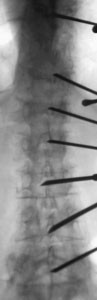

Fig. 1.